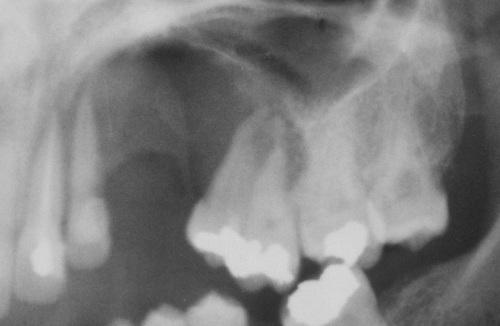

A unilocular radiolucent cyst involving the crown of an unerupted tooth, with the crown projecting into the cystic cavity.

dentigerous cyst, central type